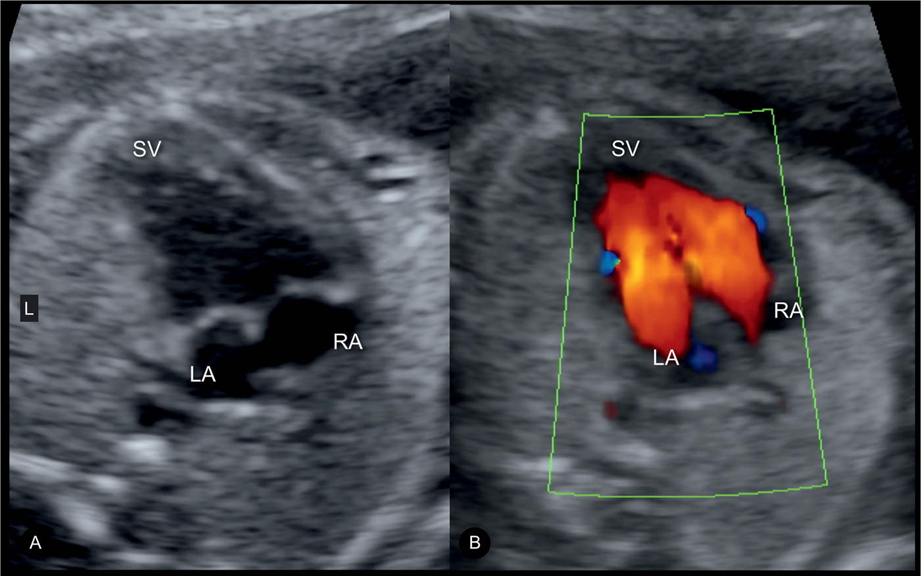

Blockage in Aortic Arch

Hypoplastic Left Heart Syndrome